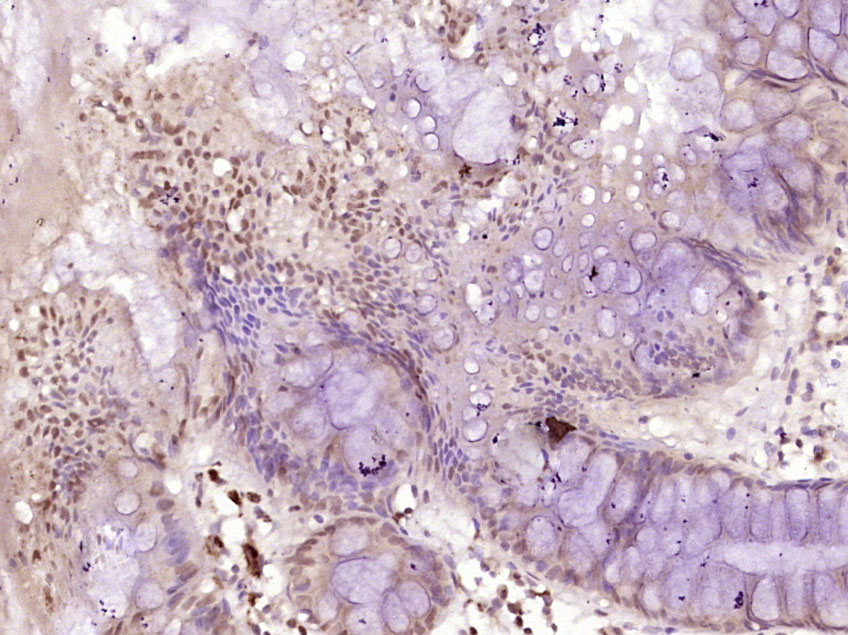

Paraformaldehyde-fixed, paraffin embedded (Rat colon); Antigen retrieval by boiling in sodium citrate buffer (pH6.0) for 15min; Block endogenous peroxidase by 3% hydrogen peroxide for 20 minutes; Blocking buffer (normal goat serum) at 37°C for 30min; Antibody incubation with (MSH6) Polyclonal Antibody, Unconjugated (bs-3804R) at 1:400 overnight at 4°C, followed by operating according to SP Kit(Rabbit) (sp-0023) instructionsand DAB staining.